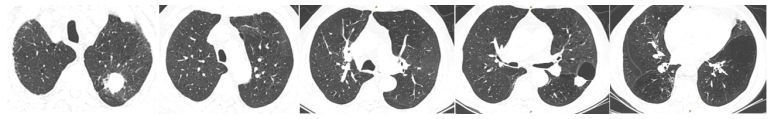

2023年5月24日多排CT胸部平扫CT所见:左肺上叶多发空洞,较前明显进展;右肺下叶支气管壁增厚伴条索影,两肺支气管旁多发絮状影及结节影,局部较前稍明显;左侧少许胸腔积液,伴左肺膨胀不全(图3)。

2023年5月26日NGS回报毛霉,经过讨论,建议艾沙康唑、两性霉素B雾化+静脉滴注、奥马环素200 mg ivd首剂,100 mg qd治疗。艾沙康唑200 mg qd+两性霉素B静滴(5月26日两性霉素B胆固醇硫酸酯复合物100 mg qd,5月27日换用两性霉素B脂质体150 mg→250 mg→350 mg qd)+两性霉素B 12.5 mg bid雾化+奥马环素100 mg qd(200 mg ivd首剂)。2023年6月5日复查胸部CT:弥漫性病变明显吸收,左上肺病灶明显呈现机化限制,病灶体积没有扩大;左肺出现新的实变影(图4)。从病灶性质上看,似乎是机化的过程,加之患者临床症状明显改善,经过讨论认为该方案是有效的,所以继续使用该治疗方案。慢性阻塞性肺疾病伴急性加重;肺真菌病(曲霉、毛霉);呼吸衰竭;糖尿病;高血压;低蛋白血症;低钾血症;颈椎术后(脊髓型颈椎病);腰椎间盘突出。①奥玛环素片300 mg/片,每日一次。②两性霉素B每日两次,每次25 mg雾化吸入。2~3月后改每天雾化一次,一次半支(12.5 mg)。③艾沙康唑20 0mg qd,维持30 min。④两性霉素B脂质体350 mg qd 60 min以上滴完。易低钾,注意监测血钾。2023年6月25日出院后复查胸部CT:病灶基本吸收,左下叶出现新病灶,边缘光滑,考虑原有肺大泡内充填了一些渗出性病变(图5)。但并未将其定义为一个新的病变,因为它不像典型的曲霉或毛霉感染的新发病变特征,并且患者症状非常逍遥,所以仍沿用原方案继续治疗。